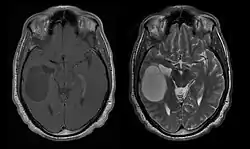

Computertomografie (CT) en magnetische resonantiebeeldvorming (MRI) kunnen neoplasie in de hersenen effectief detecteren. MRI is gevoeliger dan CT voor het identificeren van laesies, maar heeft contra-indicaties voor patiënten met pacemakers, incompatibele prothesen, metalen clips en andere. CT blijft de voorkeursmethode om calcificaties in laesies of boterosie van het kalotje of de basis te detecteren. Het gebruik van contrastmiddelen, die gejodeerd zijn in het geval van CT en paramagnetisch (gadolinium) in het geval van MRI, maakt het verkrijgen van informatie over de vascularisatie en integriteit van de bloed-hersenbarrière mogelijk, een betere definitie van de tumorachtige tumor vergeleken tot het omringende oedeem en het genereren van hypothesen over de mate van maligniteit. Het radiologisch onderzoek maakt ook een beoordeling mogelijk van de mechanische effecten en de daaruit voortvloeiende veranderingen in hersenstructuren als gevolg van de tumor, zoals hydrocefalus en hernia's, waarvan de effecten fataal kunnen zijn. Ten slotte kan deze diagnostiek, ter voorbereiding op een operatie, worden gebruikt om de locatie van de laesie of de infiltratie van de tumor in vitale delen van de hersenen te bepalen. Voor dit doel is MRI efficiënter dan CT omdat het driedimensionale beelden kan opleveren. Diagnostische radiologische beeldvormingshulpmiddelen benadrukken de verandering in neoplastisch weefsel in vergelijking met normaal hersenparenchym (door veranderingen in elektronisch afgebeelde weefseldichtheid op CT en signaalintensiteit op MRI). Zoals de meeste pathologische weefsels zijn tumoren ook herkenbaar aan een verhoogde ophoping van intracellulair water. In het computertomogram lijken ze hypodens, dwz met een lagere dichtheid dan het hersenparenchym, in het kernmagnetische resonantietomogram met spin-roosterrelaxatie hypointenseen in spin-spin ontspanning evenals proton weging (PD) hyperintens.

Computertomografie van de hersenen toont typisch een weefselmassa die door beide contrasten kan worden versterkt. Op CT lijken laaggradige gliomen gewoonlijk isodense aan het normale parenchym en vertonen daarom mogelijk geen contrastversterking. Evenzo zijn laesies in de achterste schedelgroeve moeilijk te identificeren op CT. Bijgevolg zijn de resultaten van een dergelijke tomografie alleen niet altijd voldoende voor diagnostische doeleinden. In twijfelgevallen is het gebruik van de meer gevoelige magnetische resonantiebeeldvorming essentieel.

Aan -MRI toont een intracraniële tumor als een massieve laesie die na gebruik van het contrastmiddel meer luminescent kan worden. Er is echter altijd een signaalafwijking in -Magnetic resonance imaging, die de aanwezigheid van neoplasie of vasogeen oedeem aangeeft. Gewoonlijk is verhoogde luminescentie (contrastversterking) indicatief voor een tumor met een hogere graad van maligniteit. Kenmerkend voor glioblastoom is een contrastring, waarbij het lichtgevende deel overeenkomt met het vitale deel van de kwaadaardige tumor en het donkerdere -hypointens gebied dat overeenkomt met weefselnecrose.

Diffuse astrocytomen II verschijnen op computertomografie. Cijfers dan minder intense laesies. In de geprefereerde magnetische resonantiebeeldvorming zijn contrastmiddelen mogelijk niet in staat om deze neoplasmata te markeren, hun luminescentie kan dunner en zwakker zijn. Een meer intense kan wijzen op weefsels met verhoogde anaplasie. Waar mogelijk wordt een biopsie voorgesteld om monsters van het anaplastische deel van de tumor te verkrijgen.